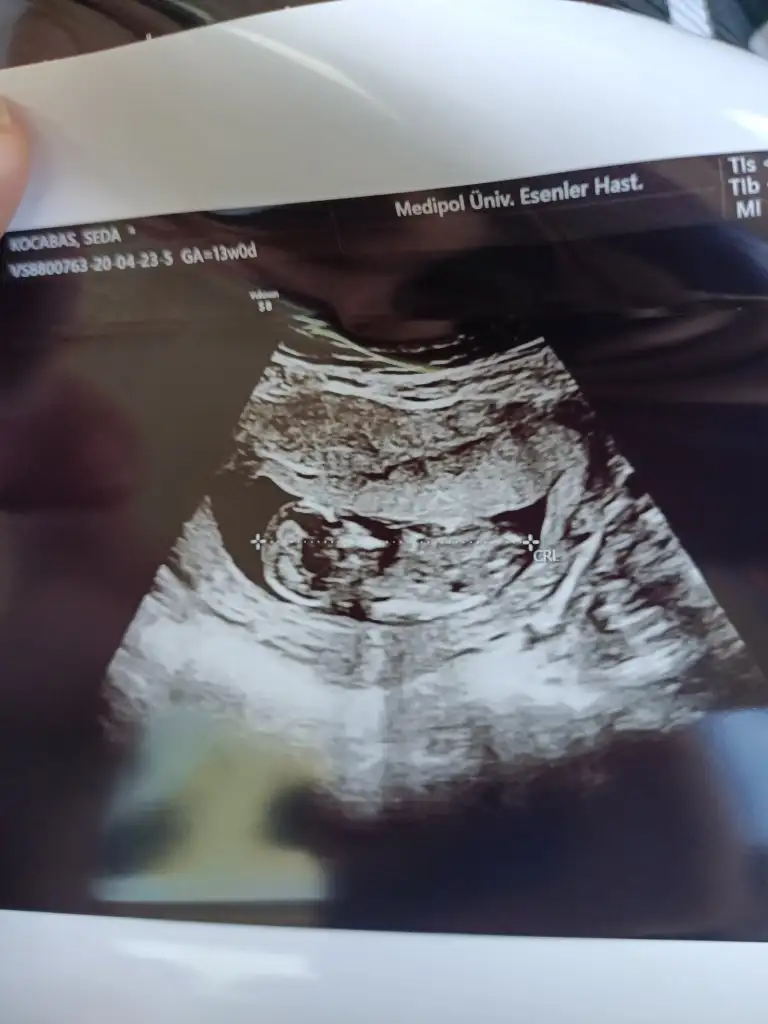

Merhabalar anlayanlar benim görüntülerede bakabilirmi 13 haftalık olduk merak ediyorum 😉

Eklentiler

• IMG20200422153547.webp

IMG20200422153547.webp

25,6 KB · Görüntüleme: 54